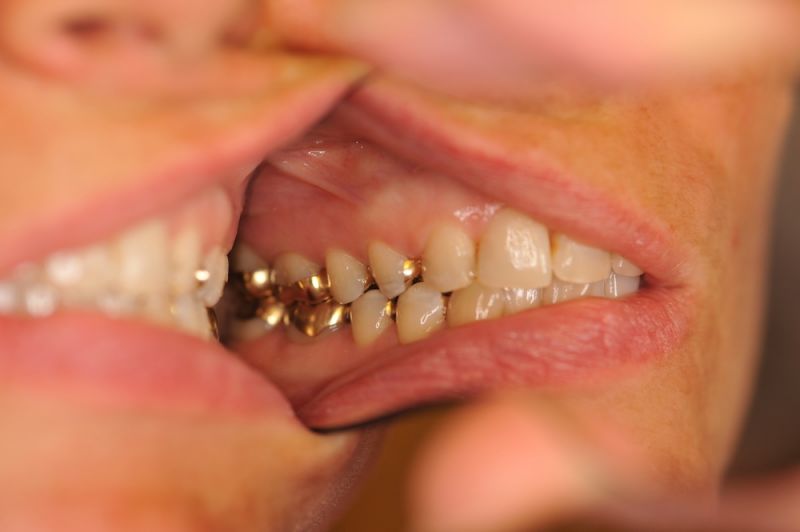

Patientin aus Uelzen zum Recall

11346

Wir würden gerne mal was Neues zeigen, es gibt nur nichts Neues.

Die Arbeit befindet sich seit 23 Jahren unverändert im Munde der Patientin!